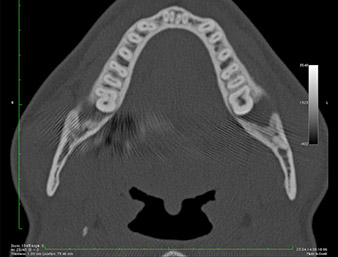

With adequate preoperative radiological diagnostics (orthopantomogram), injuries to the inferior alveolar nerve are mostly foreseeable and therefore preventable. Where it is suspected that an impacted third molar is in close proximity to this nerve, a three-dimensional image (DVT, CT) may additionally be indicated (6, 7).

It could be seen in the 3D image (digital volume tomography) that the root remnant was located disto-caudally in the transition from the horizontal to the ascending portion of the mandible (Fig. 2).

Based on his medical history, our patient (non-smoker, 26 years old) had a very good chance of a successful outcome. Due to indication of the root remnant’s close proximity to the inferior alveolar nerve on the OPG, digital volume tomography was used in addition (6).

The very close proximity discovered made it necessary to perform a precise and atraumatic osteotomy. In this case, clinical observations and comparative studies favour piezo surgery which has been available since the end of the 1990s (9-11). Due to the characteristic micro-oscillation of these systems, it is possible to remove bone selectively, thus enabling minimally invasive preparation.